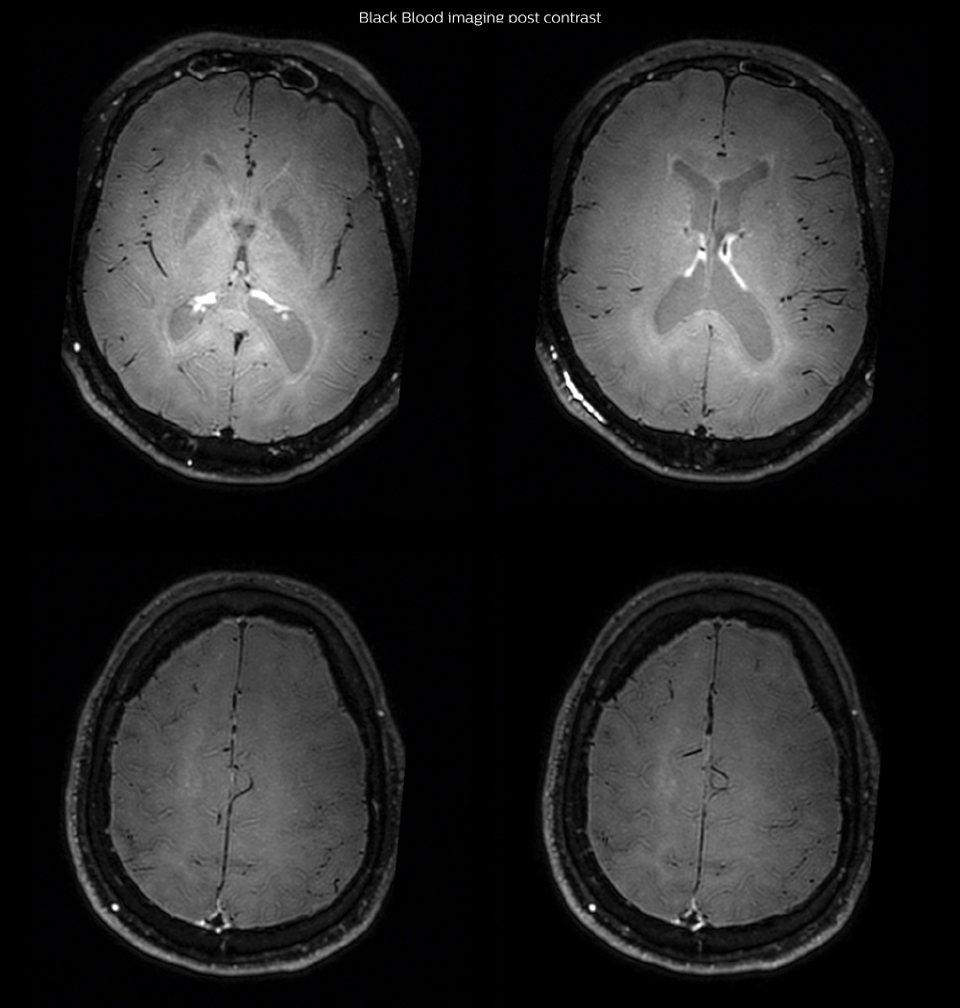

After a conventional routine MR imaging examination, the suspicion of vasculitis arose, therefore we performed an MRI including Black Blood imaging in a separate session. The dedicated ExamCard includes diffusion, FLAIR, MR angiography using TOF, and 3D T1 MRA with bolus injection. This ExamCard also includes Black Blood imaging before and after contrast. This examination was performed on our Ingenia 3.0T. Black Blood scan time 4:39 min, acquired voxel size 0.75 x 0.75 x 1.0 mm, 21 slices.

had, such as glucose intolerance, arterial hypertension and hypocholesteremia, his lesions could be atherosclerotic lesions or vasculitis, conditions which require different treatment. Especially in this patient with HIV infection causing the vasculitis, treatment of the two conditions is different. The results of MRI with Black Blood imaging, helped to choose the preferred treatment for this patient, which was based on antiviral medication rather than an antiaggregant or anticoagulation treatment which is usually given to patients with risk of ischemia based on atherosclerotic lesions. One month after beginning the antiviral treatment, the same MRI examination was repeated and again 8 months after the beginning of treatment. On follow-up images, we see the enhancements have almost disappeared. So in case of this patient, the MRI exam with Black Blood imaging helped us to give the patient the appropriate treatment and also allowed us to noninvasively confirm the treatment response.

After one month of treatment, post-contrast Black Blood images at the exact same levels as in the figure above show disappearance of the vessel wall enhancements which were seen on the previous examination.